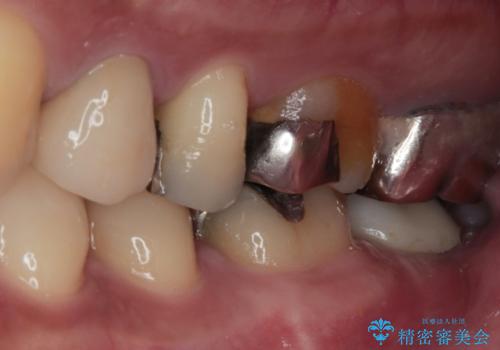

- 左下の歯が欠けてしまったとのことで来院された患者様です。

大きな銀歯が装着されており、その周りからむし歯が広がっている状態でした。

特に症状はなく、神経組織も健全な状態であったため、むし歯を全て取り切った後にフルジルコニアクラウンにて補綴することとしました。

銀歯などを使用する保険診療は、歯との境界の適合が悪く、むし歯の再発リスクが高いため、長期的な観点から使用は推奨されません。